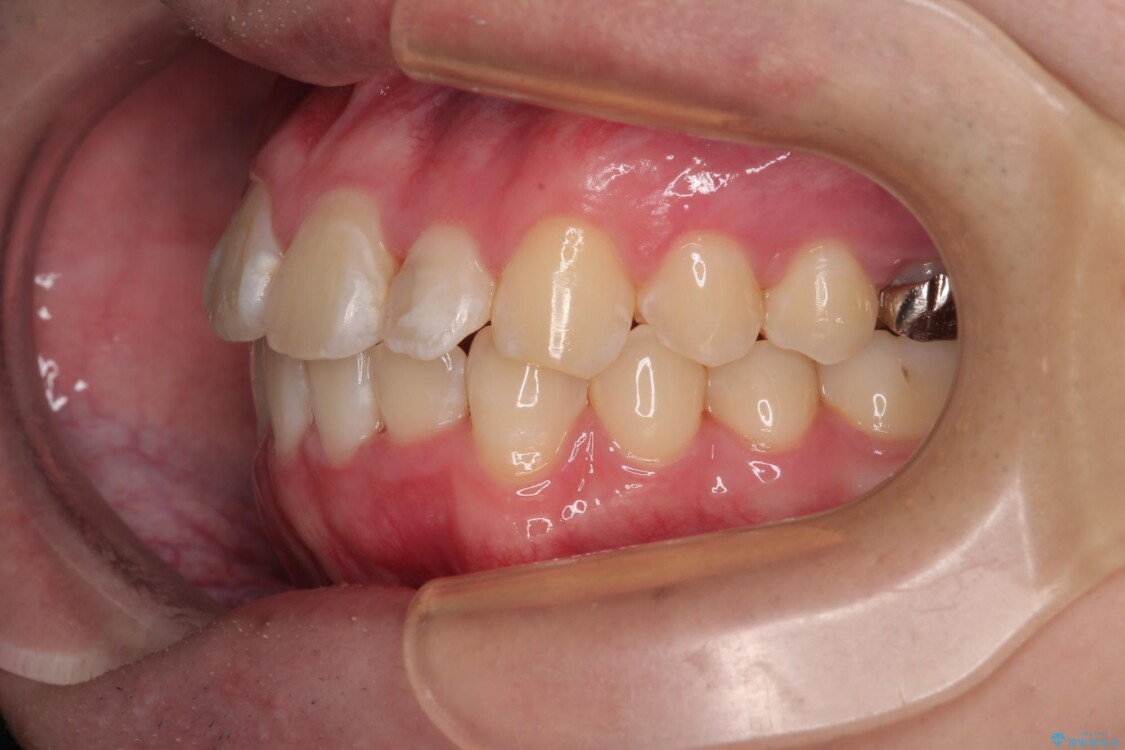

治療後について

適切な診断と装置の選択により、1年という短期間でここまで改善できます。

治療後

• 1年でここまで変わる!歯列のがたつきと正中のズレを改善した矯正治療(メタルブラケット×MARPE) 治療後画像